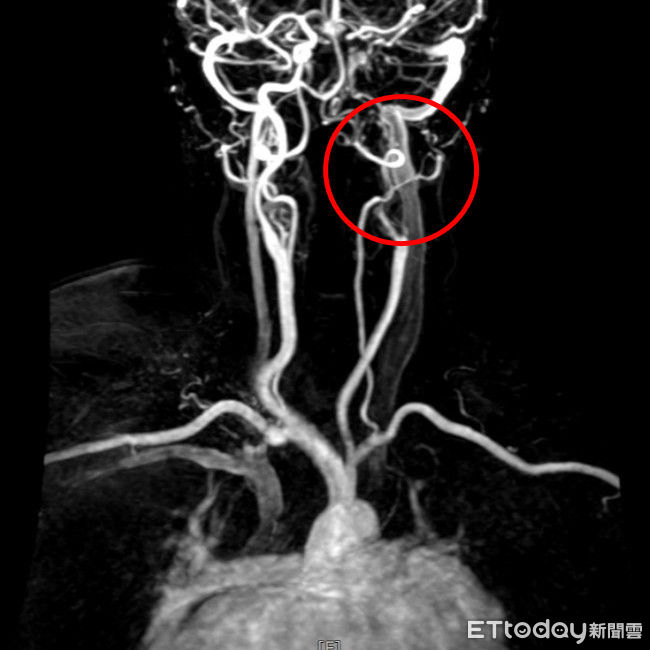

▲甘女士經核磁共振檢查發現缺少左側內頸動脈的顯影,顯示左側內頸動脈完全阻塞。

腦中風臨床表現包括平衡感、視力或手腳肌力下降,或是臉部或嘴角的歪斜、口齒不清等,甘女士的兒子因職業原因相當警覺,察覺到媽媽的症狀疑似腦中風,雖右手和右腳尚能行動,但握力明顯變差,因此果斷將病人送醫。救護車抵達急診後,醫療團隊立即為病人做電腦斷層檢查,排除出血型腦中風,並做核磁共振,發現左腦有明顯發亮區域,以及缺少了左側內頸動脈的顯影,即確認是左腦急性腦塞與左側內頸動脈完全阻塞。